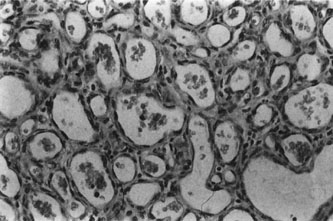

Histopathology

Infantile capillary hemangiomas have a characteristic histopathologic pattern with masses of plump proliferating endothelial cells organized into a network of basement membrane–lined vascular channels with small, irregular lumina (Fig. 4). No true capsule exists.10 A reticulin stain may help delineate primitive vascular structures in early stages of proliferation when there are few vascular spaces.10 During the proliferative phase or for poorly differentiated tumors, the localization of von Willebrand factor produced by the endothelial cells by either peroxidase or fluorescent antibody technique may prove useful.10 Lesions undergoing involution are characterized by fewer endothelial cells, larger and less numerous vascular channels, increasing collagen deposition, intralesional fat, and in some instances, inflammatory cell infiltrates. The late regression phase is dominated by fibrosis.10

Fig. 4. Infantile capillary hemangioma. Characteristic pattern of masses of plump endothelial cells organized into a network of basement membrane-lined vascular channels with small, irregular lumina. Red blood cells are present within these spaces (H&E, ×250).